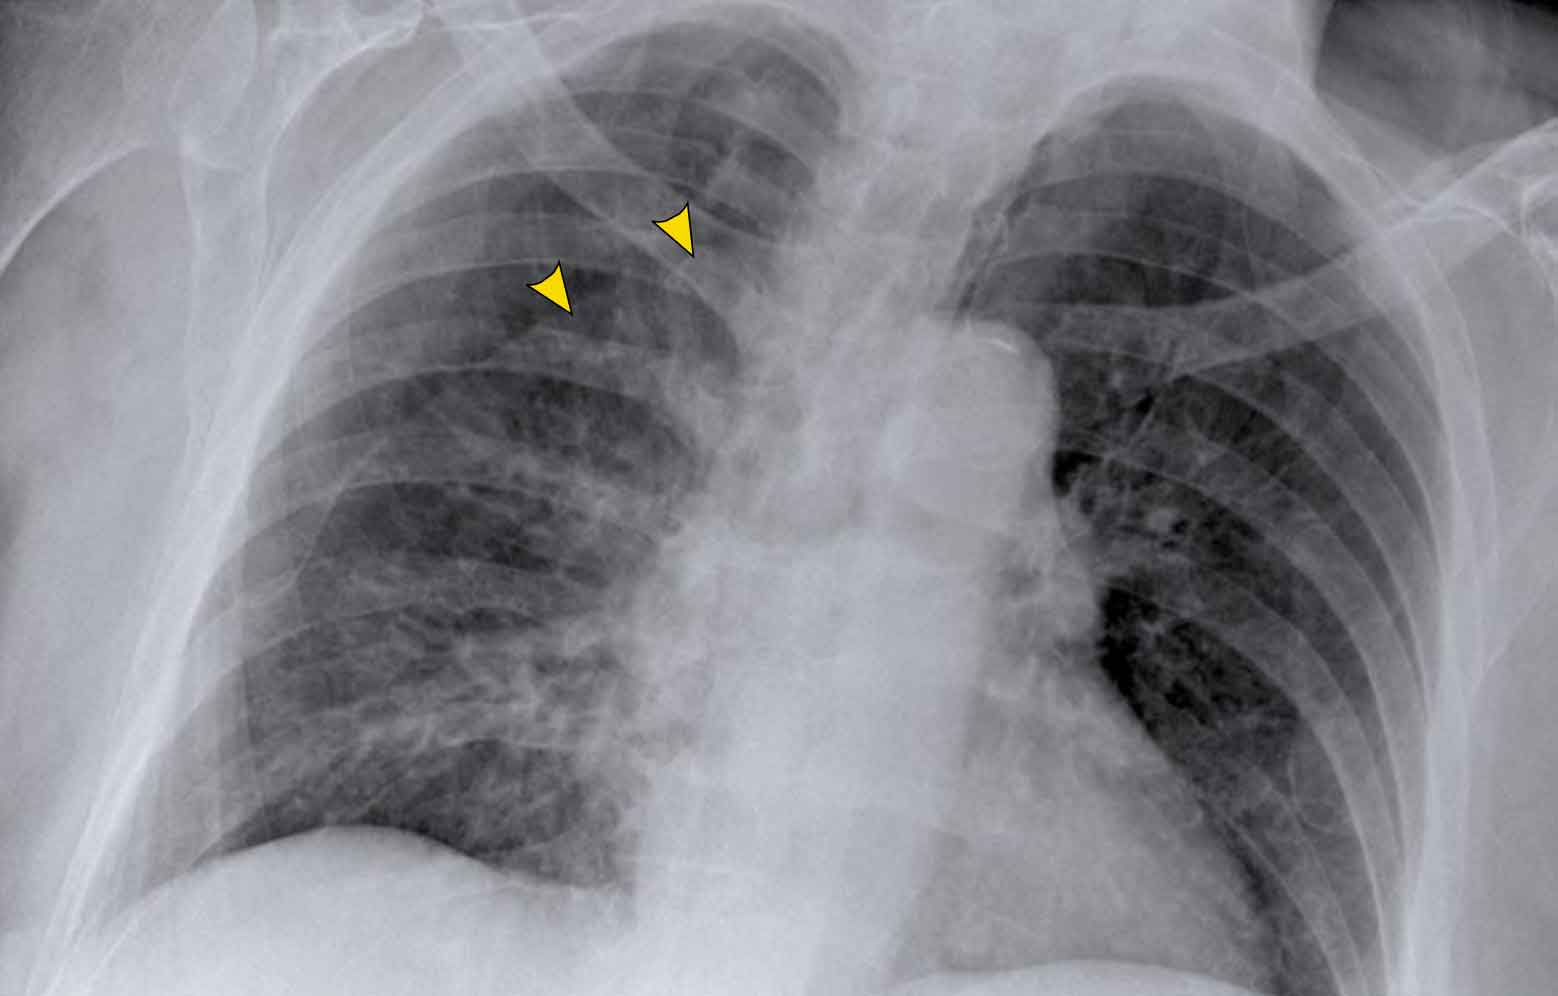

Vena azygos lobe, seen as a fine line that crosses the apex of the right lung. Vena azygos lobe, seen as a fine line that crosses the apex of the right lung.

Vena azygos lobe

A common normal variant, the azygos lobe, is formed when the azygos vein takes an anomalous lateral course, creating a deep pleural fissure in the upper lobe of the right lung.

On radiographs, it appears as a thin curvilinear line traversing the right upper lung field, frequently ending in a teardrop-shaped density (the azygos vein) within the azygos fissure.

Here another patient with an azygos lobe.

The azygos vein is seen as a thick structure within the azygos fissure.